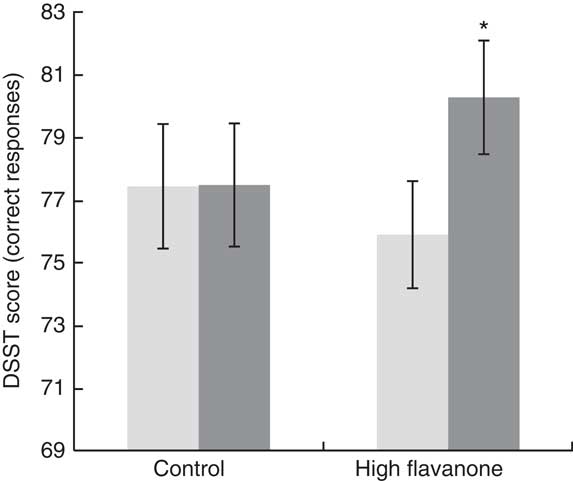

A significant drink×time interaction was observed for the DSST (F 1,23=10·76, P<0·01). As shown in Fig. 2, post hoc t tests revealed that consumption of the HF drink resulted in a significant improvement in DSST performance at 2 h relative to baseline (t=3·84, P<0·01), whereas no significant improvement in performance was observed following the CT drink (t=0·05, P=0·96). Baseline DSST performance did not differ between the CT and HF drinks (t=0·02, P=0·98). No significant interactions or main effects were observed for all other cognitive tests (see Table 2).

Fig. 2 Digit Symbol Substitution Test (DSST) mean correct responses and standard errors for the control and high flavanone drink at baseline and 2 h after consumption. Following a significant drink×time interaction (F

1,23=10·76, P<0·01), post hoc tests revealed that the number of correct responses on the DSST was significantly greater at 2 h (![]() ) relative to baseline (

) relative to baseline (![]() ) (t=3·84, P<0·01) following consumption of the flavanone-rich juice. *Mean value was significantly different from that at baseline (P<0·05; post hoc test).

) (t=3·84, P<0·01) following consumption of the flavanone-rich juice. *Mean value was significantly different from that at baseline (P<0·05; post hoc test).